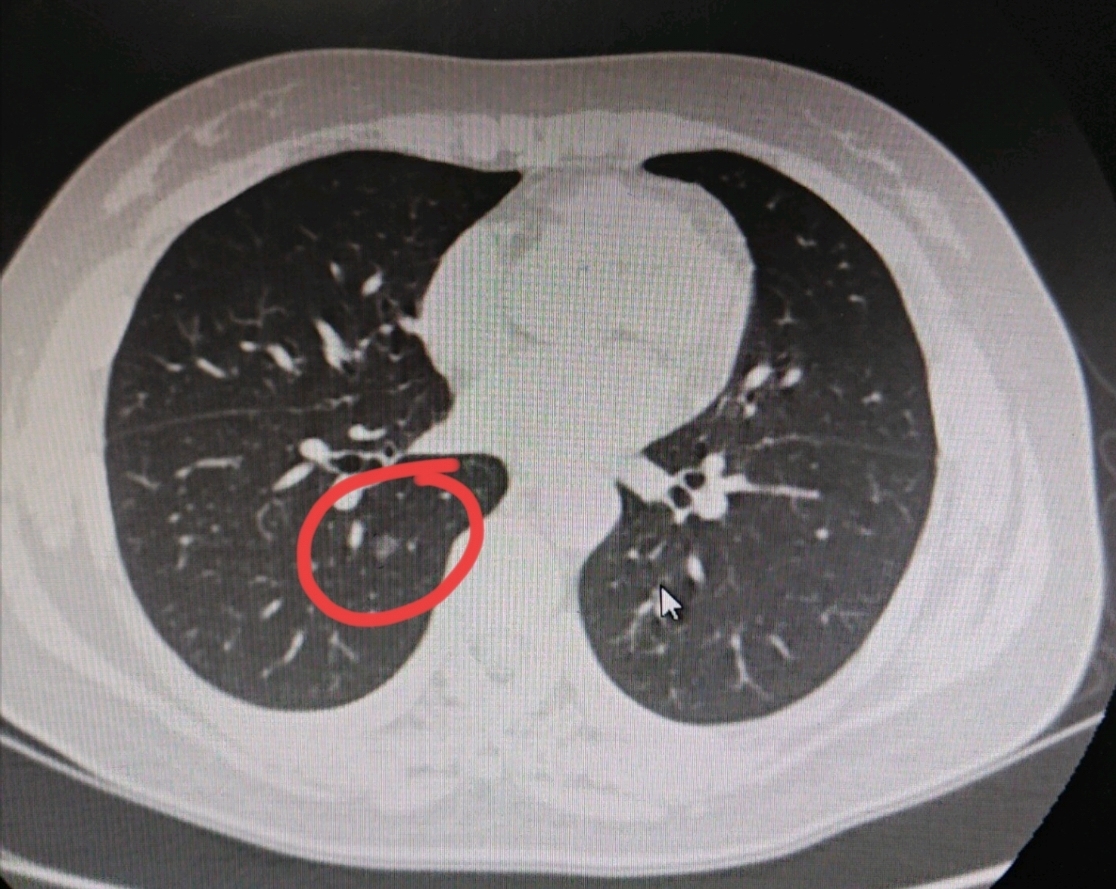

肺部結(jié)節(jié)

在我平時的診療工作中,肺磨玻璃結(jié)節(jié)是接觸最多的病種,我也給大家分享了很多在我這里做手術(shù)的肺磨玻璃結(jié)節(jié)的病例。有很多的朋友在這些病例下面發(fā)表評論,想了解這些患者有什么不舒服?

在之前,我給大家講過,對于直徑比較小的磨玻璃結(jié)節(jié)型肺癌來說,患者可以感覺到一切正常,沒有任何的不舒服,都是在查體或者因為其他疾病拍片子時候偶然發(fā)展。實際上,別說比較小的磨玻璃結(jié)節(jié)型肺癌,就是有的比較大的肺癌,甚至我治療過有的長到十厘米的肺癌,病人都沒有任何的不舒服。所以我一再強調(diào),不能以現(xiàn)在身體沒有癥狀,就能排除自己沒長肺癌,更不能排除自己的肺結(jié)節(jié)不是肺癌。但很多朋友的心態(tài)就是這樣,專業(yè)醫(yī)生說的話他覺得不靠譜,只相信自己的身體感覺,因此把自己肺癌耽誤的大有人在。